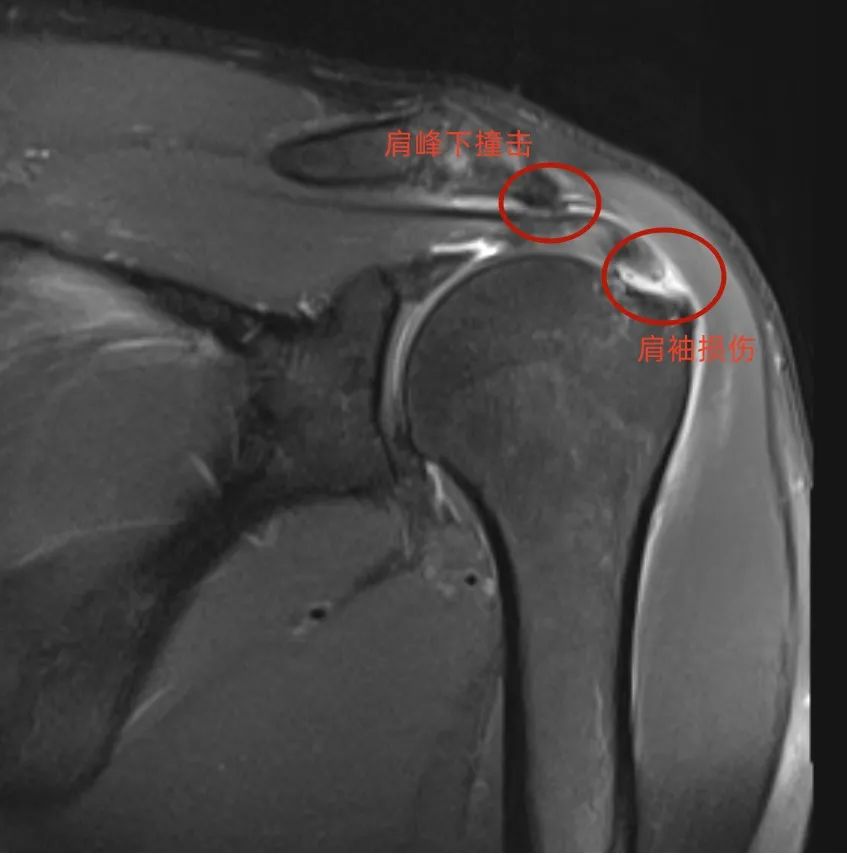

近日,经朋友介绍,不堪困扰的仲大爷慕名来到我院骨科就诊。吴勇主任接诊后详细询问病史,并根据自己多年的临床经验,为其安排了核磁共振检查。检查结果提示:仲大爷肩袖损伤、肩峰下撞击、粘连性肩关节囊炎等。